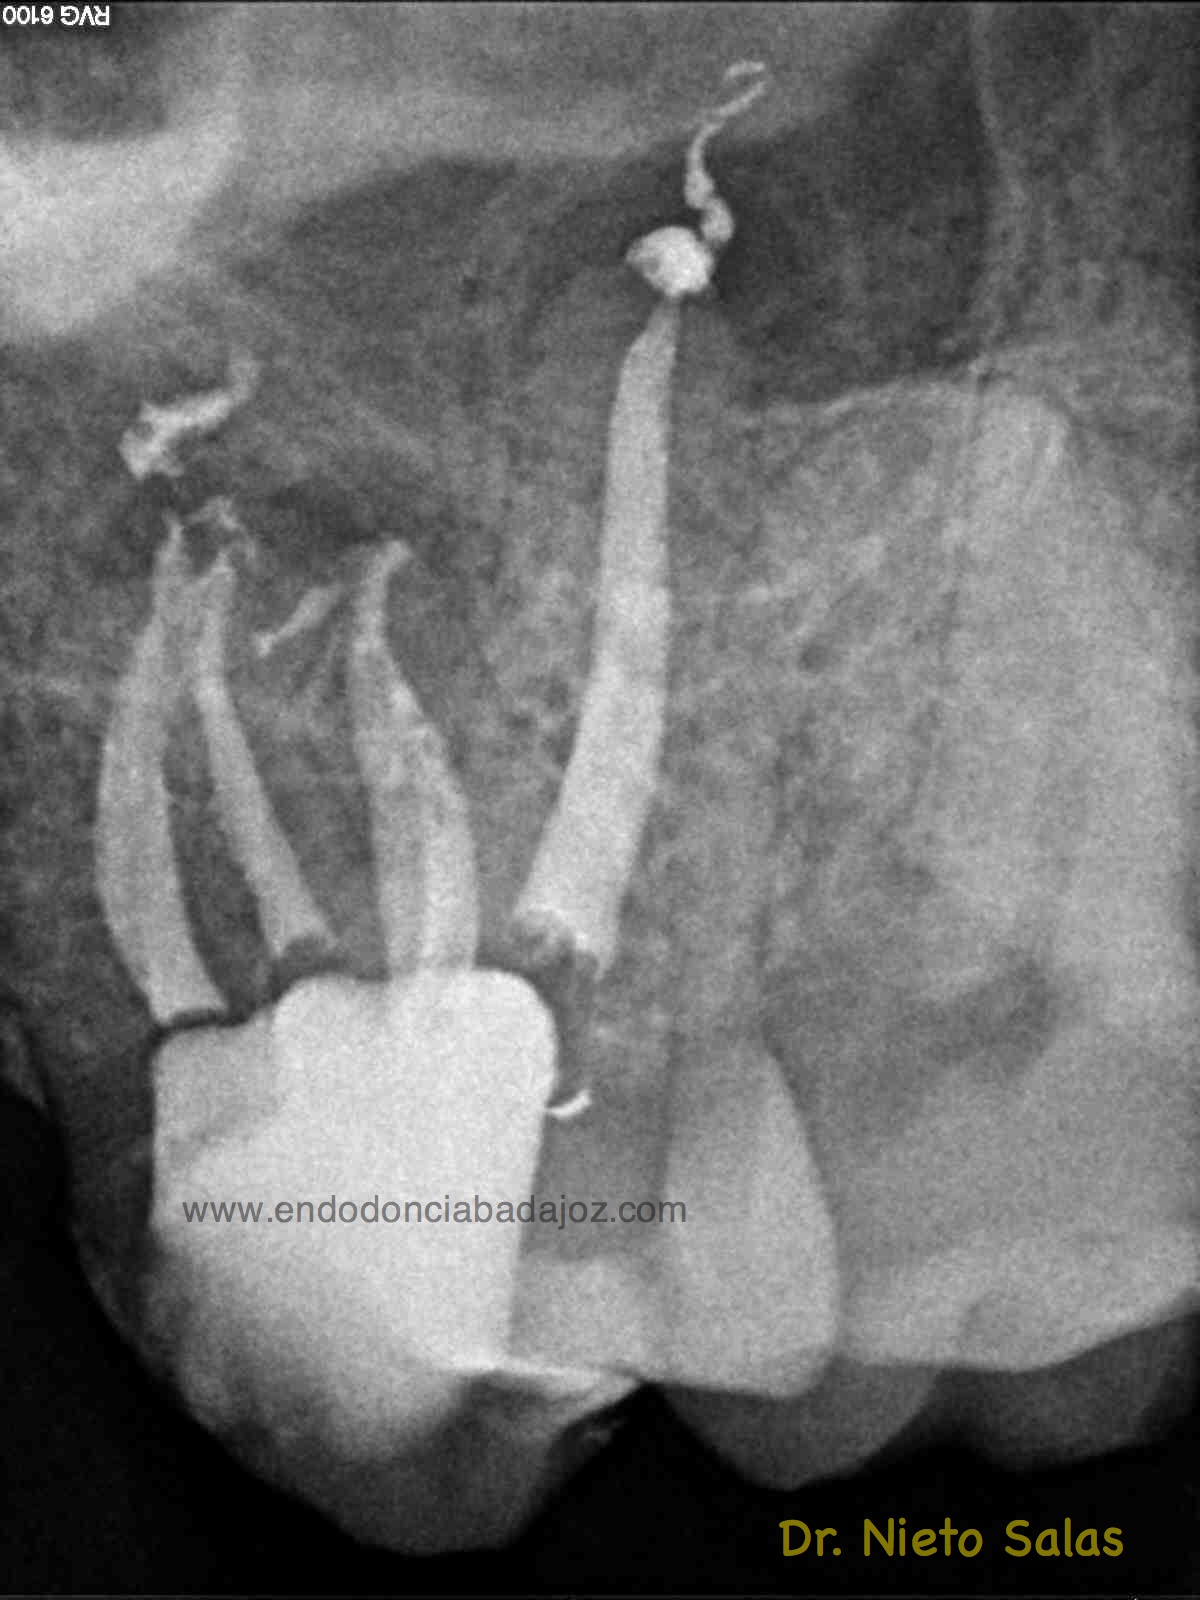

Os presento unos casos de varios molares superiores, con tres conductos mesiovestibulares con un foramen o con dos.

Una vez que tenemos medidas, obturamos los conductos:

No es habitual en nuestra práctica casos como estos, pero os pongo algunos más:

Sabemos que unas de las piezas que más fracasan, son estas piezas, pues, sin la ayuda de magnificación, es muy probable que dejemos alguna zona del sistema sin limpiar y mucho menos, obturarla.